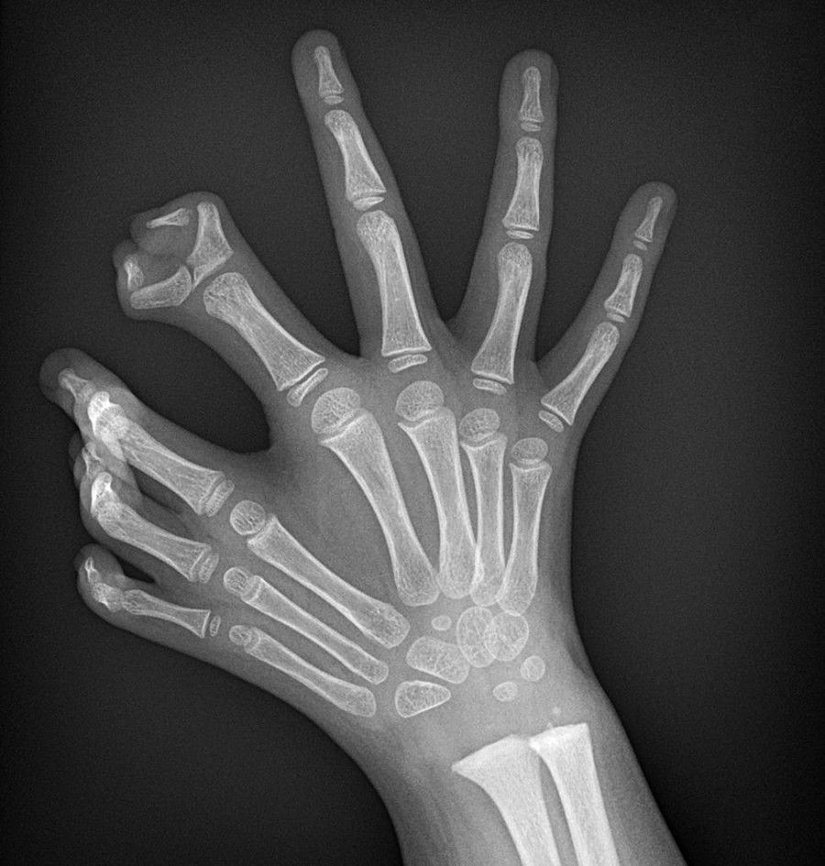

Bu gördüğünüz, "ulnar dimelia" adı verilen ve yaygın olarak "ayna el sendromu" olarak bilinen, nadir görülen kalıtsal hastalığa ait bir X-ray taraması görüntüsüdür. Bu hastalığa sahip kişilerin işaret parmakları ile başparmakları bulunmaz; bunun yerine diğer üç parmakları ayna simetrisine uygun bir şekilde çiftlenmiştir. Kişilerin ellerinin ayna görüntüsündeki parmaklar tam gelişmiş ve işlevseldir.

Hastalık, el ve kol gibi uzuvlarda gelişimsel anomaliler ve yamukluklar şeklinde kendini gösterir. Buna bağlı olarak bilekte de sertlik ve katılaşma görülebilir. Uzuvlardaki yamulma, kemiklerde meydana gelen uzunluk farklarına bağlı olarak yaşanır.